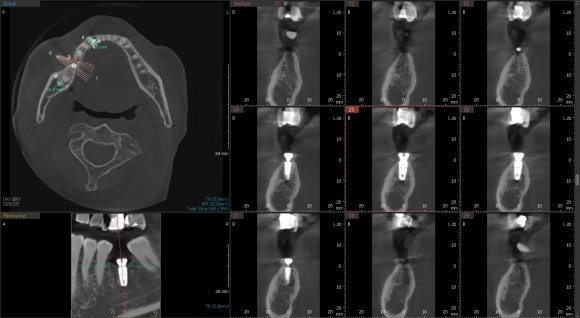

20241220

임플란트 수술을 한 후 즉시 CT를 촬영했습니다.

원하는 각도로 정확히 삽입되었는지

정밀하게 확인하기 위해서요.

매 수술마다 환자분과 함께 CT를 확인합니다.

수술 직전까지 이미지트레이닝하던 결과가

CT 상에 그대로 구현되면 정말 뿌듯합니다^^